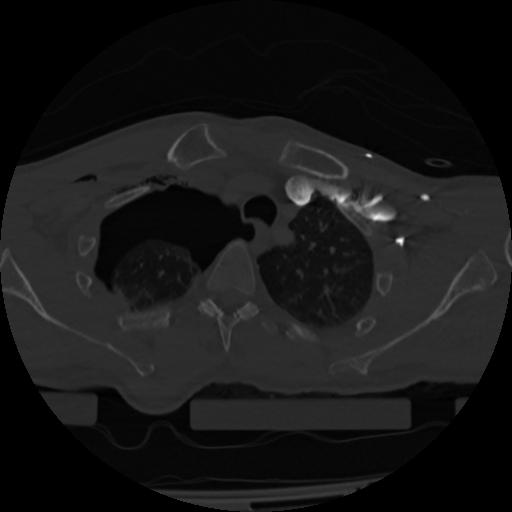

22 ANGIO,CE,Vol,0.5,ANGIO,,